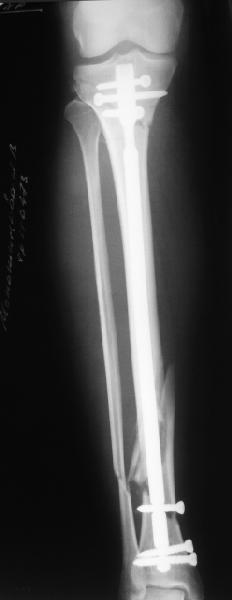

Alexander Chelnokov 22 Май 2006, 00:35

Сделали все-таки стержнем. На всякий случай просверлил дополнительное проксимальное отверстие, так что получилось три 45-градусных винта.

В дистракторе провеи спиц поболше в прокисмальном отделе, чтобы не разобщить фрагменты при сгибании колена. Комментарии и критика приветствуются.

We proceeded with nailing using a small wire distractor, with few wires at the proximal end to prevent displacement with forced knee flexion. Images attached. Comments and critics are welcome.